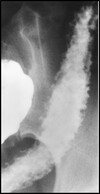

What pathology is shown here?

Tracheaoesophageal fistula

What are the white arrows pointing to?

The airway

What pathology is seen here?

Tracheoesophageal Fistula

What are the radiographic signs of a Tracheoesophageal Fistula?

-Connection of the fistula between airway and esophagus

-Large dilation of the esophagus